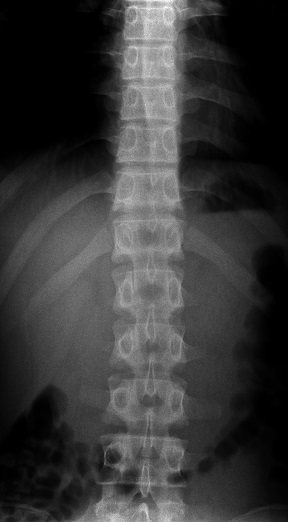

坂戸市若葉 中学生 腰が痛い 腰痛

レントゲン 正面像 レントゲン 斜位像

坂戸市若葉 中学2年生男子。 腰の痛み、腰痛。

小学生からサッカーのクラブチームに所属しています。半年前から腰が痛くて練習が思い切って

整骨院や整形外科で治療を受けてきましたが、腰の痛みは無くなりませんでした。当接骨院で

腰の痛みが半年と長かったのでいつも精査を依頼しているクリニックでレントゲン検査を実施

いたしました。腰椎の分離症やすべり症が心配でしたが、特に骨格にはに問題はありませんでした。

【治療】

やはり腰や股関節周囲の筋肉の緊張が非常に高まっていました。それらの筋肉を徹底的に柔軟に

していきます。当院独自の特殊仕様の治療機器を使用していきます。

男子はこれまでも日常的な腰痛とギックリ腰に悩まされてきましたが、腰部や股関節回りの

筋緊張を緩和することによって体感のバランスも調整され、将来の腰の痛みで椎間板ヘルニア

などの症状も予防できます。

半年間の痛みが数週間で消失しました。現在はクラブチームの練習を100%の力で行うことが

できています。男子のサッカーのパフォーマンスを最大限に引き上げるために、治療を継続中です。

当接骨院では場合によっては、整形外科や総合病院での検査を依頼することもあります。患者様には

なるべく負担の掛からない範囲で必要に応じて医療機関を紹介しております。